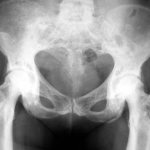

На рентгеновском фото-снимке: Болезнь Педжета тазобедренного сустава

Изменения костей таза зависят от соотношения резорбции и остеогенеза; характерно уплотнение костной ткани по верхней апертуре таза. На остеосклеротической стадии можно наблюдать равномерное уплотнение костей лицевого черепа, реже — позвонков. При этом тела позвонков могут напоминать слоновую кость (эбурнеация). Похожая картина наблюдается при лимфогранулематозе, но при нем пораженные позвонки не увеличиваются в размерах.